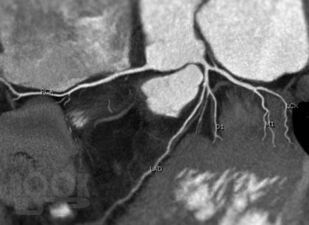

Достоинствами метода МСКТ-КГ являются неинвазивность и возможность оценить не только просвет коронарной артерии, проходимость аортокоронарных шунтов и стентов, но и состояние стенки сосуда, структуру атеросклеротической бляшки, а также возможность визуализации полостей сердца, миокарда и анатомических структур в зоне исследования.